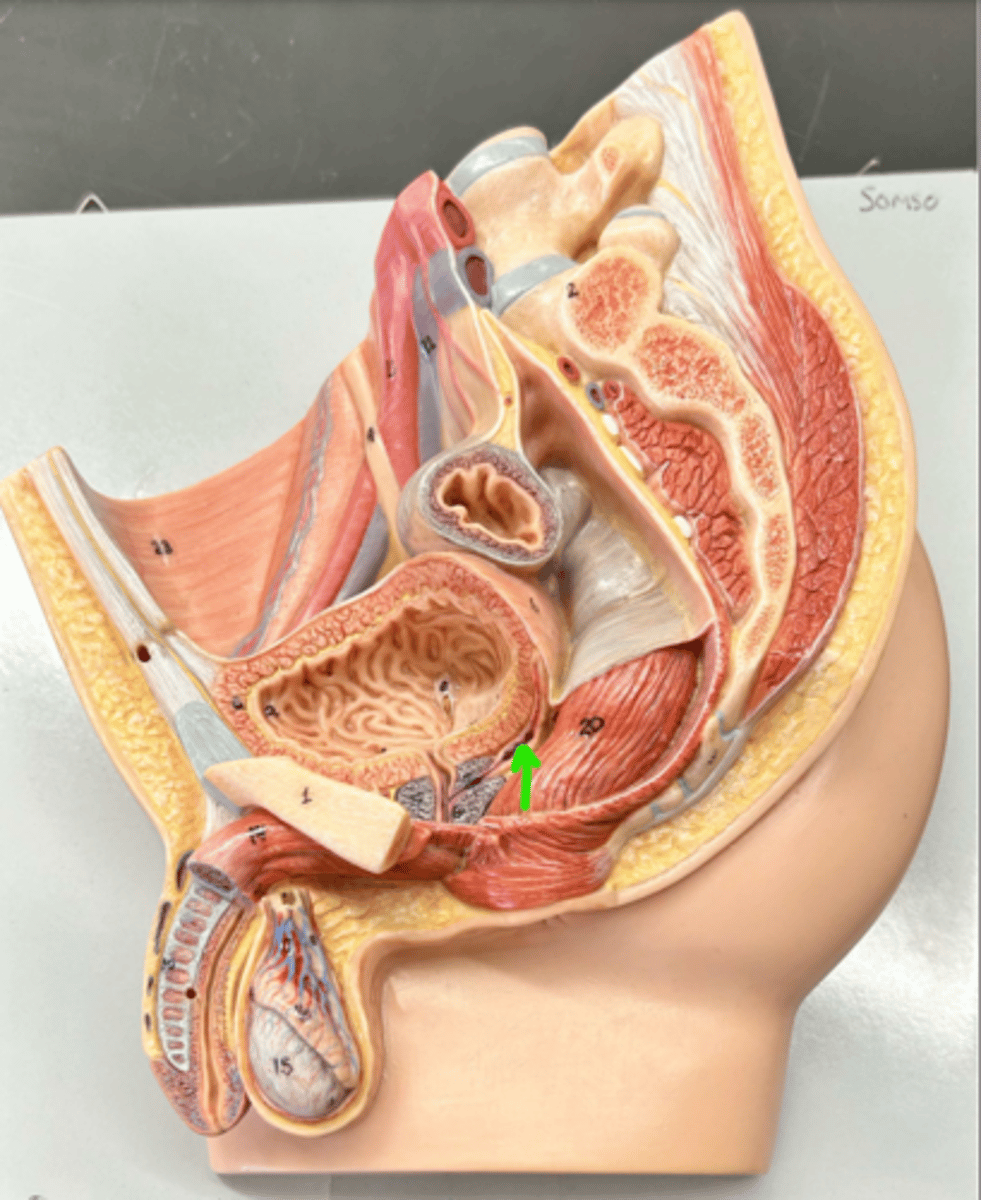

Prostate gland

Bulbourethral gland

Urethra

Urethra

Prostatic urethra

Membranous urethra

Spongy urethra